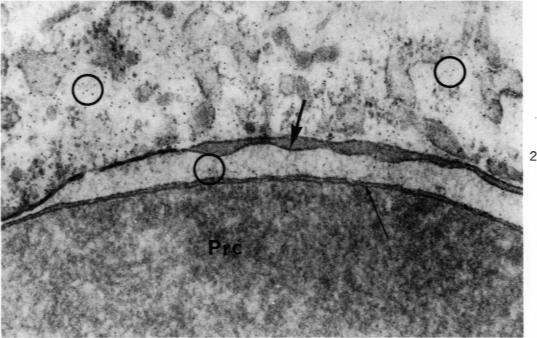

Electron microscopy of the spleen. 3. Erythro-leukophagocytosis.

Am J Pathol. 1970 Mar;58(3):451-70.